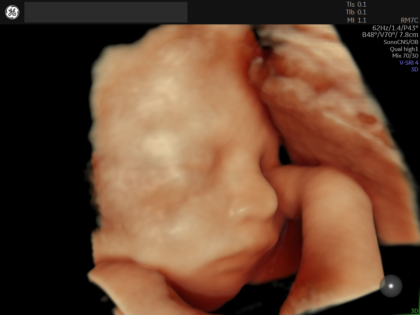

最新の4Dエコー

GE社の Expert22 BT25 を導入しております

最新の4Dエコー機器「GE Expert22 BT25(Voluson Expert 22)」は、産婦人科領域に特化したハイエンド超音波装置で、2D・3D・4Dすべてにおいて非常に高精細な画像描出が可能です。独自の次世代エンジンにより、胎児の顔や臓器の細かな構造まで鮮明に可視化でき、従来よりもリアルで立体的な映像をリアルタイムに確認できます。また、AIによる自動計測や画像補正機能により、検査の精度と再現性が向上し、診断の質を高めることが可能です。さらに、胎児心臓や脳などの詳細評価にも対応しており、異常の早期発見や適切な管理につながります。これにより、妊婦さんにとっては安心感の高い健診を提供でき、医療者にとっても効率的かつ高度な診療を実現する先進的なエコー機器です。

超音波エコー映像